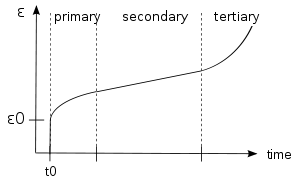

Stretching before exercise will affect the cartilage through "creep". It will place a constant load on the labrum, allowing fluid the leak out and deform to the applied load. This is significant for the viscoelasticity of the labrum.[18] The hip labrum acts as a shock absorber, joint lubricator, stabilizer and pressure distributor.[4] With this essential warm up, it is possible for it to be better prepared to prevent a hip labrum tear. Body weight squats are a great example of stretching and warming up the body to induce creep before exercise.

This man is doing a body weight squat. There are no added weights to his body, allowing him to warm up his legs properly. This is a great way to induce "creep" in the cartilage and muscles to prepare for intense exercise. Strain vs. Time graph for the three stages of creep. Strain slowly rises up and almost becomes constant from a constant stress on a viscoelastic material. Like your cartilage, it will deform or strain, from constant stress. The strain deformation is slow, but eventually too much stress will increase it.

Strain vs. Time graph for the three stages of creep. Strain slowly rises up and almost becomes constant from a constant stress on a viscoelastic material. Like your cartilage, it will deform or strain, from constant stress. The strain deformation is slow, but eventually too much stress will increase it.